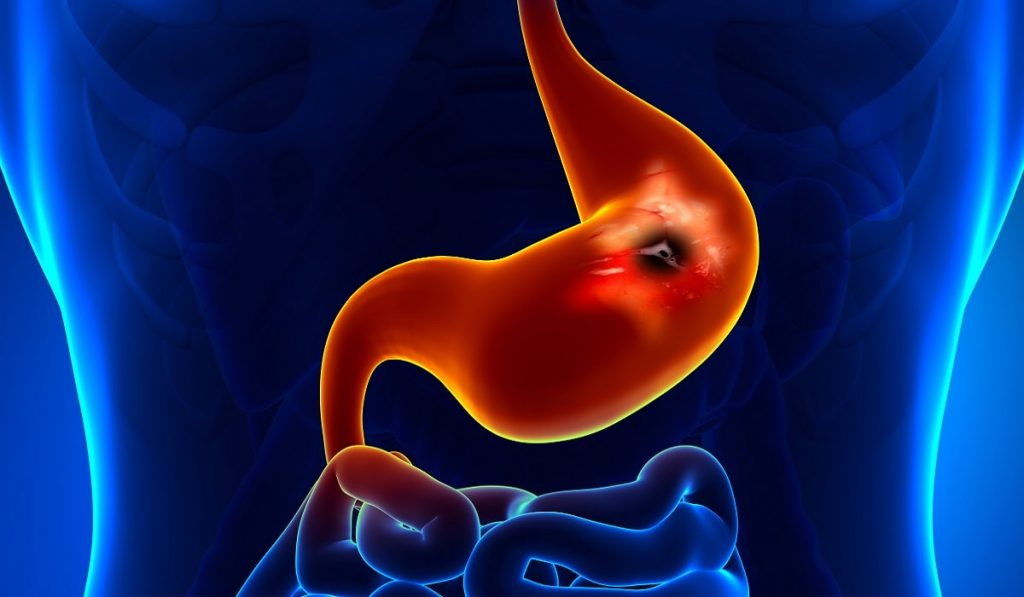

Mide kanseri dünya genelinde bakıldığında en sık görülen 4. kanser türüdür. Ülkemizde ise her yıl yaklaşık 20 bin gibi çok ciddi bir sayıda kişi bu kansere yakalanmaktadır. Kanser konusuyla ilgili yayımladığımız diğer yazılarımızda olduğu gibi, bunda da öncelikle mide denilen organı tanıyarak işe başlayalım. Mide kaslardan oluşan, alınan besinlerin geçici olarak depolandığı bir sindirim sistemi organıdır. Kaburgaların altında, karının üst bölgesinde yer alır.

Yemek borusu ile ince bağırsak arasında yer alan mide en az 1,5 litre, en fazla 4 litre su tutma kapasitesine sahiptir. Ağız yoluyla alınan besinler özefagus yani yemek borusu vasıtasıyla mideye ulaşır. Buraya ulaşan yiyecekler fiziksel ve kimyasal bir parçalanmaya uğrar. Midenin iç yüzeyi mukoza adı verilen bir tabaka ile örtülüdür. İçerisinde besin olan bir mide her 20 saniyede bir dalgalanma hareketi yaparak, besini parçalama işlemini gerçekleştirir.

Mide Kanseri Nedir?

Bir sindirim sistemi organı olan midede meydana gelen kansere mide kanseri adı verilir. Genellikle bir ülser şeklinde başlayan mide kanseri oldukça hızlı yayılım göstermektedir. Bu yüzden ne kadar erken tanı konur ve tedaviye başlanırsa hastanın bu kanserden kurtulma ihtimali o kadar artar.

Bir sindirim sistemi organı olan midede meydana gelen kansere mide kanseri adı verilir. Genellikle bir ülser şeklinde başlayan mide kanseri oldukça hızlı yayılım göstermektedir. Bu yüzden ne kadar erken tanı konur ve tedaviye başlanırsa hastanın bu kanserden kurtulma ihtimali o kadar artar.

Çeşitli sebeplerle ortaya çıkan mide kanseri midenin mukoza zarında oluşan tümörler ile kendini göstermektedir. Hastalık en hızlı ilerleyen ve yayılan kanser türlerinden biridir. Direkt kan yoluyla veya lenfatik yolla yayılabilmektedir. Dünyadan en sık görülen 4. kanser türü olan mide kanserinin ülkemizdeki görülme sıklığı da oldukça fazladır.